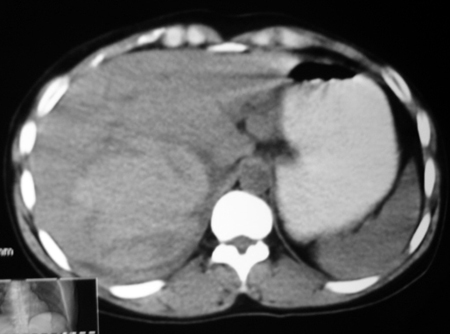

以下是引用bmw011在2009-4-23 13:28:00的发言:[br]考虑右肾包膜下血肿。

以下是引用卜一在2009-4-23 15:43:00的发言:[br]考虑右肾包膜下血肿,不排除占位病变伴出血可能,建议进一步检查。